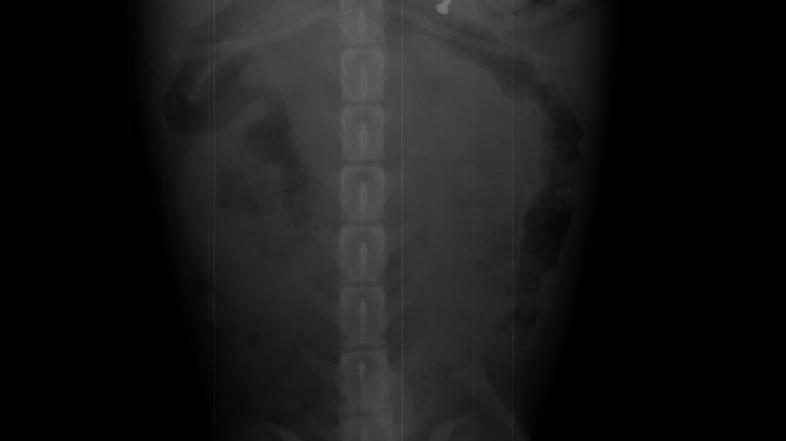

Kuža manekenke in voditeljice Tjaše Kokalj je pojedel žebelj, zaradi česar je moral pod nož.

Tjaša Kokalj se je pred kratkim močno ustrašila za zdravje svojega štirinožnega prijateljčka, psička Kukija. Kosmati lepotec je namreč pojedel žebelj, ki ga ni mogel izločiti po naravni poti, zato so ga morali veterinarji naslednji dan operirati. "Videla sem, kako je Kuki pojedel žebelj, ki je padel na tla. Če tega ne bi videla, sploh ne bi vedela, da je z njim nekaj narobe. Ves čas se je namreč obnašal povsem normalno," nam je izdala Tjaša, ki je s kužkom takoj pohitela k veterinarju. "Rada bi se zahvalila ekipi Medicoveta za hitro in prijazno odzivnost,“ nam je še povedala Tjaša in priznala, da bi bila še bolj panična, če ob njej ne bi bilo fanta in tako prijaznih veterinarjev.

Izvedeli smo še, da se Kuki, ki ima osem šivov, po operaciji počuti že veliko bolje.